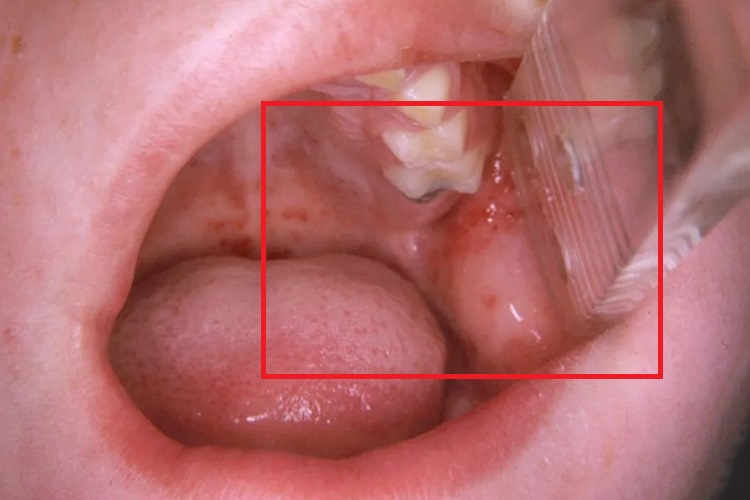

腮腺炎:炎症早期,症状轻微或不明显,腮腺区轻微疼痛、肿大、压痛。导管口轻度水肿、疼痛,从而使口腔两侧颊黏膜水肿。随着疾病的进一步发展,炎症会扩散到腮腺周围组织,伴发蜂窝组织炎。

腮腺炎:炎症早期可以局部热敷、理疗,或者遵医嘱外敷如意金黄散,还可使用碳酸氢钠溶液等漱口剂进食漱口,有助于炎症的控制。同时根据导管口脓性分泌物的药敏试验,选择最敏感的抗生素,若已发展至化脓时,必须切开引流。